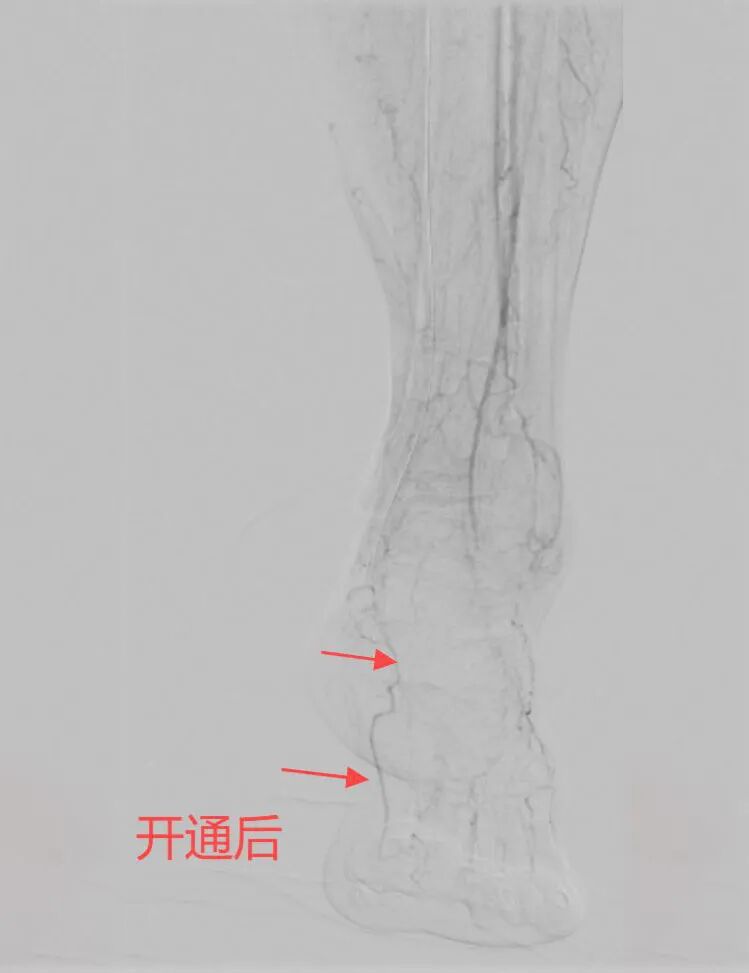

入院后,由血管外科姚松良副主任医师主刀,为张奶奶开展手术“复活”了血管。术中造影显示张奶奶的膝下动脉几乎全部闭塞,仅剩侧支循环在维持,大拇指周围几乎没有血管。经过两个小时的手术,患者血流重新涌入“荒漠”,左大拇指血运恢复。术后当晚,张奶奶的脚终于有了久违的暖意,疼痛烟消云散,她笑着说:“这是半年来第一次睡到天亮!”